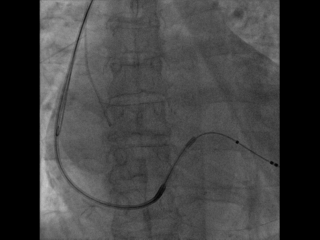

选择哪根靶静脉?

选择后侧静脉,Runthough导丝顺利通过并与心中静脉交通回到右心房,但左室4298电极无法通过狭窄处。

因4298外径在5.3F,故选用Maverick2.0X15mm预扩球囊在狭窄处给予充分扩张

扩张后电极仍无法通过

尝试心中静脉,但血管扭曲,导丝进入困难

尝试侧静脉,但远端过于狭窄,电极无法完全进入分支,测试结果不理想,只能放弃该血管

再次尝试后侧静脉,改用Sprinter Legend2.5X15mm预扩球囊扩张,可见明显腊肠样狭窄,给予28atm时方可见完全扩张

电极仍然无法通过,造影发现狭窄依然存在

尝试鞘中鞘试图通过狭窄处,但电极仍然无法通过

尝试Quantum Maverick3.0X12mm后扩球囊进行扩张

电极依然无法通过狭窄处,放弃手术?